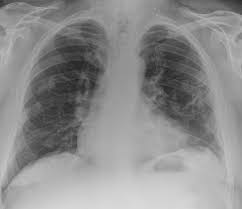

Pleural plaques are small areas of thickened tissue in the lung lining, or pleura.

There are innumerable pleural plaques, seen mostly en face. Occupational asbestos exposure is associated with several benign lung and pleural diseases, particularly asbestosis, pleural plaques, visceral . Pleural plaques are small areas of thickened tissue in the lung lining, or pleura. Therefore, pulmonary fibrosis associated with pleural . Pleural plaques were defined as areas of pleural thickening. Pleural plaques are observed in most cases of asbestosis (98.5%) but not ipf (p < 0.001). Experience in the field of asbestos related radiological changes. Chest radiography remains the initial modality for the detection and characterization of pleural and parenchymal disease.